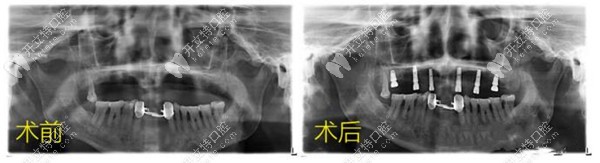

種植牙前后對比